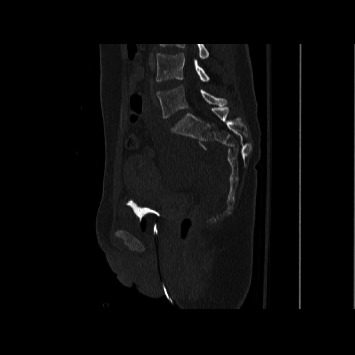

导读:脊柱骨盆分离是一种毁灭性的损伤,由于其复杂性和低发病率,仍然难以管理。腰椎骨盆固定是一种传统的治疗选择,采用开放入路。然而,在严重的多发创伤患者中,开放式固定与大量失血和感染风险相关。技术的进步使得这种手术可以经皮进行。因此,我们评估了接受开放式腰骨盆固定和接受经皮腰骨盆固定的患者之间的结果。方法:回顾性分析2012年至2024年接受开放或经皮腰骨盆固定治疗脊柱骨盆分离的患者。采用AOSpine分类系统对所有骨折进行分类。分析患者人口统计学、临床和手术结果。结果:48例脊柱骨盆分离患者纳入最终分析,其中21例接受开放式腰骨盆固定,27例接受经皮腰骨盆固定。两组患者术前特征和人口统计学相似。经皮组出血量明显减少(82 mL vs. 679 mL;P < 0.01),手术时间较短(168∶284 min;P < 0.01),手术部位感染较少(0比4;p=0.03),降低了手术室成本(35,097美元vs. 23,743美元;P =0.01),但盆腔前环损伤率较高(63% vs. 19%;p = 0.003)。两组患者的住院时间(p=0.63)和随访时间(p=0.64)均无统计学差异。结论:我们的研究结果表明,经皮腰盆腔内固定术是一种具有吸引力的微创且时间短的治疗脊柱盆腔分离的方法,而且不会增加发病率。

Introduction: Spinopelvic dissociation is a devastating injury that remains difficult to manage due to its complexity and low incidence. Lumbopelvic fixation is a treatment option traditionally performed with an open approach. However, open fixation is associated with substantial blood loss and infection risk in critical polytrauma patients. Technological advancements have enabled this procedure to be performed percutaneously. Thus, we evaluate outcomes between patients receiving open lumbopelvic fixation and those receiving percutaneous lumbopelvic fixation. Methods: A retrospective review was conducted of patients undergoing either open or percutaneous lumbopelvic fixation for spinopelvic dissociation from 2012 to 2024. The AOSpine classification system was used to classify all fractures. Patient demographic, clinical, and operative outcomes were analyzed. Results: 48 patients with spinopelvic dissociation were included in the final analysis, with 21 receiving open lumbopelvic fixation and 27 receiving percutaneous lumbopelvic fixation. Preoperative characteristics and demographics were similar between the two groups. The percutaneous group demonstrated significantly reduced blood loss (82 vs. 679 mL; p < 0.01), shorter operative time (168 vs. 284 min; p < 0.01), fewer surgical site infections (0 vs. 4; p=0.03), and reduced OR cost ($35,097 vs. $23,743; p=0.01) but had a higher rate of anterior pelvic ring injuries (63% vs. 19%; p=0.003). There was no significant difference in length of stay (p=0.63) or length of follow-up (p=0.64). Conclusion: Our findings suggest that percutaneous lumbopelvic fixation offers an attractive less invasive and shorter procedure to treat spinopelvic dissociation without added morbidity.